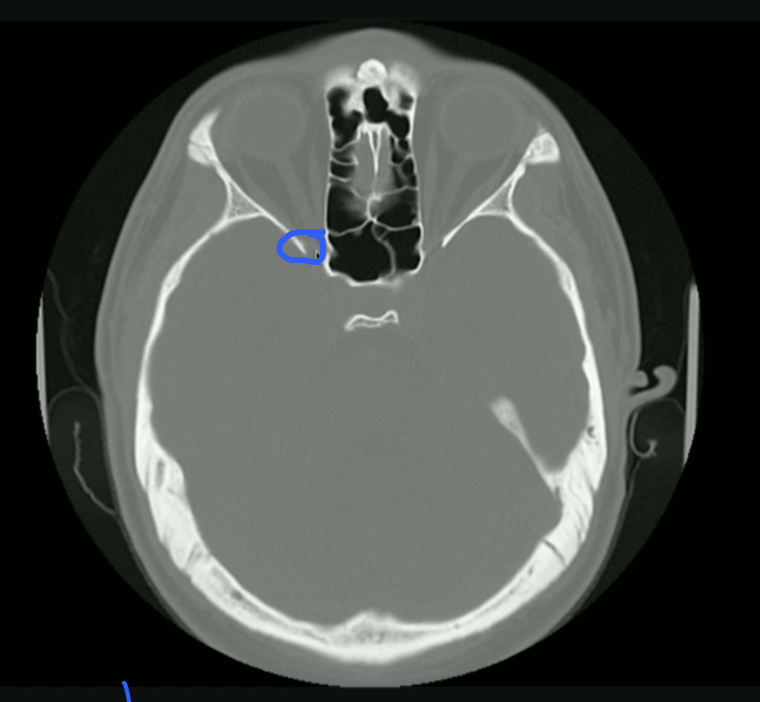

<p>What is Top + Bottom Circle + Arrow?</p>

What is Top + Bottom Circle + Arrow?

• Top: 3rd Ventricle

• Bottom: 4th Ventricle

• Arrow: Cerebral Aqueduct